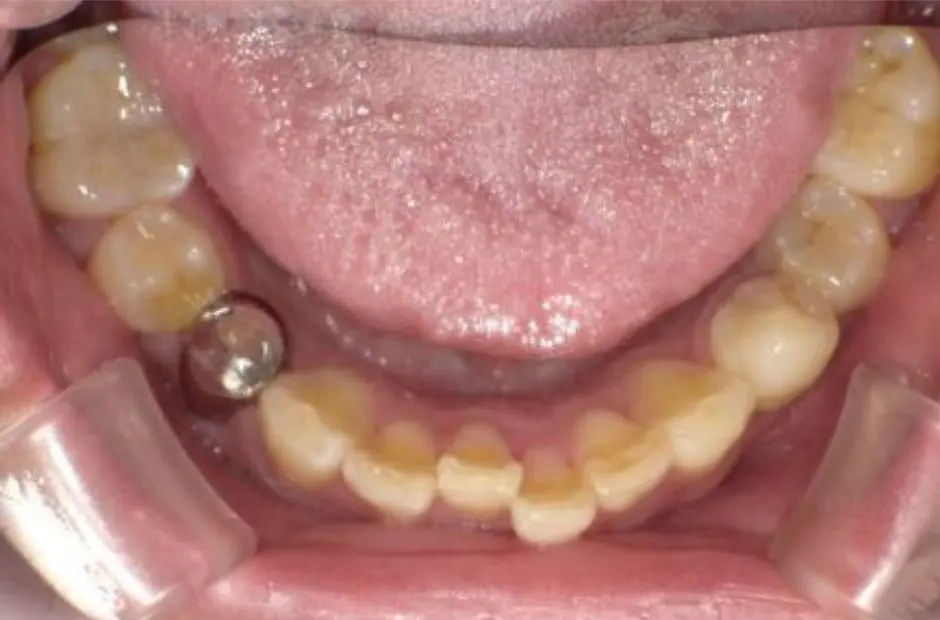

case.02

金属アレルギー治療の症例・治療前写真(銀歯7本)

金属アレルギー治療の症例・治療後写真(銀歯7本)

「 メタルフリーで、健康を手に! 」

当サロンのメタルフリー治療は、金属アレルギーの心配を排除し、健康な口内環境を実現します。高品質な非金属素材で安心と健康を手に入れましょう。

治療内容 古い銀歯を取り除き、レジンとセラミックを組み合わせて装着

治療期間/回数 2ヶ月/通院6回

施術当時の総額 220,000円(税込。検査・診断・手術関連処置費用などは含まない)。e-maxインレー:55,000円/1カ所

リスク・副作用 咬合による割れ